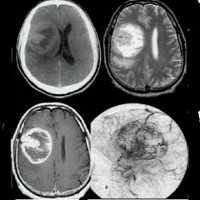

Рост и регресс мультифокальной опухоли: (А) При МРТ у пятилетнего мальчика с нистагмом и кивательными движениями головы выявлено увеличение хиазмы, более выраженное слева.

(Б) Изменения хиазмы сопровождаются двусторонним утолщением зрительного нерва, более выраженным слева.

Хорошо заметное низкоинтенсивное кольцо, более широкое слева, окружает высокоинтенсивный центральный стержень, это так называемый ложный симптом цереброспинальной жидкости.

(В) При МРТ через пять лет выявляется выраженное спонтанное уменьшение размеров хиазмальной части опухоли, теперь ее левая часть меньше правой.

Хотя нистагм исчез, сохраняется поражение зрительного нерва, острота зрения составляет 20/20 OD и 20/400 OS.

(Г) Еще через три года при МРТ с контрастированием определены нормальные размеры и плотность хиазмы.

(Г, Д) Однако сохраняются без изменений выраженное увеличение размеров и изгиб книзу обоих зрительных нервов.

На правом глазу определяется остаточная атрофия диска зрительного нерва, острота зрения, поля зрения и цветовосприятие в пределах нормы,

но на левом глазу имеется выраженная атрофия диска зрительного нерва, острота зрения снизилась до счета пальцев с расстояния двух футов, несмотря на регресс и нормализацию размеров хиазмальной части опухоли.

(Е) Еще через три года при МРТ с обеих сторон выявляется выраженное уменьшение гиперплазии орбитальной периневральной паутинной оболочки, зрительные функции на прежнем уровне.

Все же ложный симптом цереброспинальной жидкости сохраняется, при генетическом обследовании мальчика и его семьи не выявлено данных за NF1. Постнатальный рост и регресс опухоли.